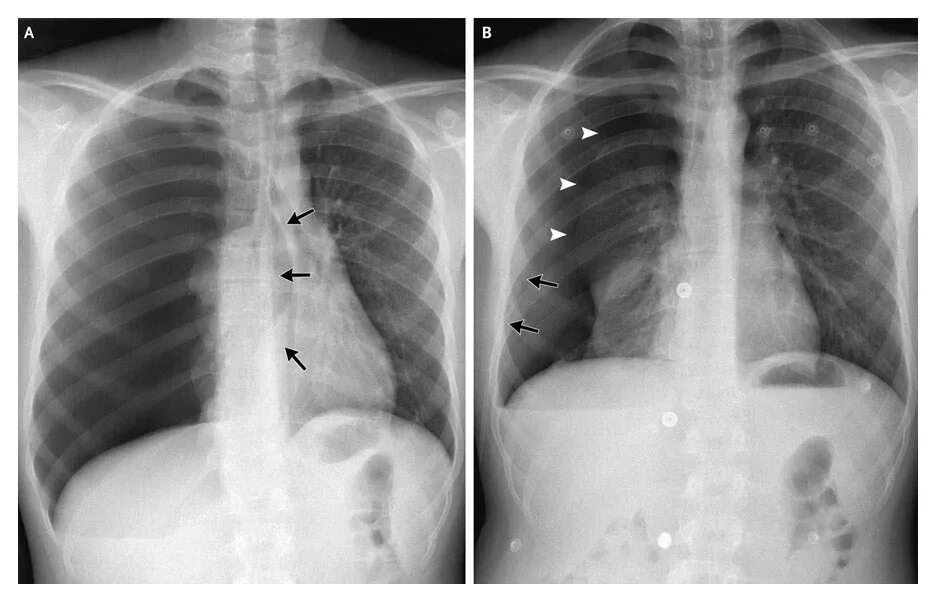

Апикальные спайки